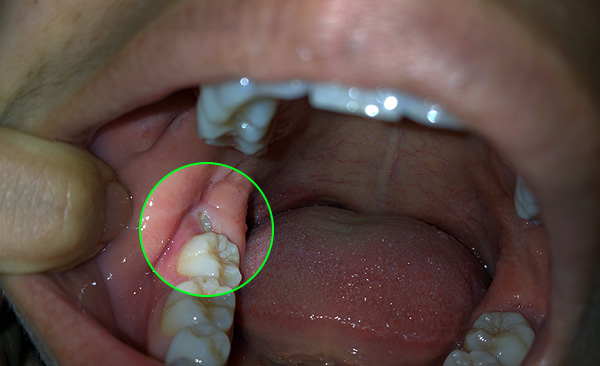

Dal punto di vista di un dentista, la situazione in cui un paziente cammina per anni con un dente cariato, distrutto alla base, appare come segue: questa persona non si dispiace per se stessa. Il fatto è che in questi casi, le radici dei denti devono essere rimosse urgentemente (vedi l'esempio nella foto sotto).

Il motivo è semplice: le radici marce sono un focolaio di infezione e più sono in bocca, più i problemi sono pronunciati e sono tutt'altro che limitati a alitosi costante. Questi "marci" porosi come un aspirapolvere assorbono da soli batteri e particelle di cibo. Oltre al cibo in decomposizione, sui residui dei denti sono presenti anche placca difficile da rimuovere e quasi sempre tartaro sopra e sottogengivale, che causa sofferenza alle gengive.

Le fotografie seguenti mostrano l'estrazione del dente, la cui parte della corona viene distrutta quasi al livello delle gengive: